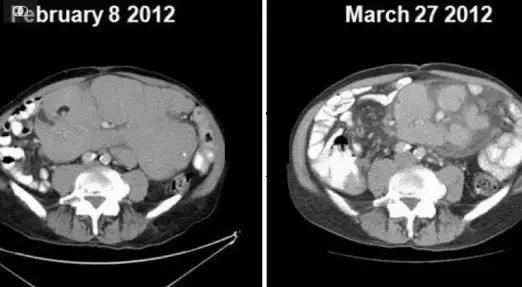

在黄教授团队的治疗下,John尝试了这款新药。

在服用该药不久后,John体内的细胞恢复了正常形态。

没错,正是因为就是这款Venclexta,疗效显著,病人病情得到了好转!